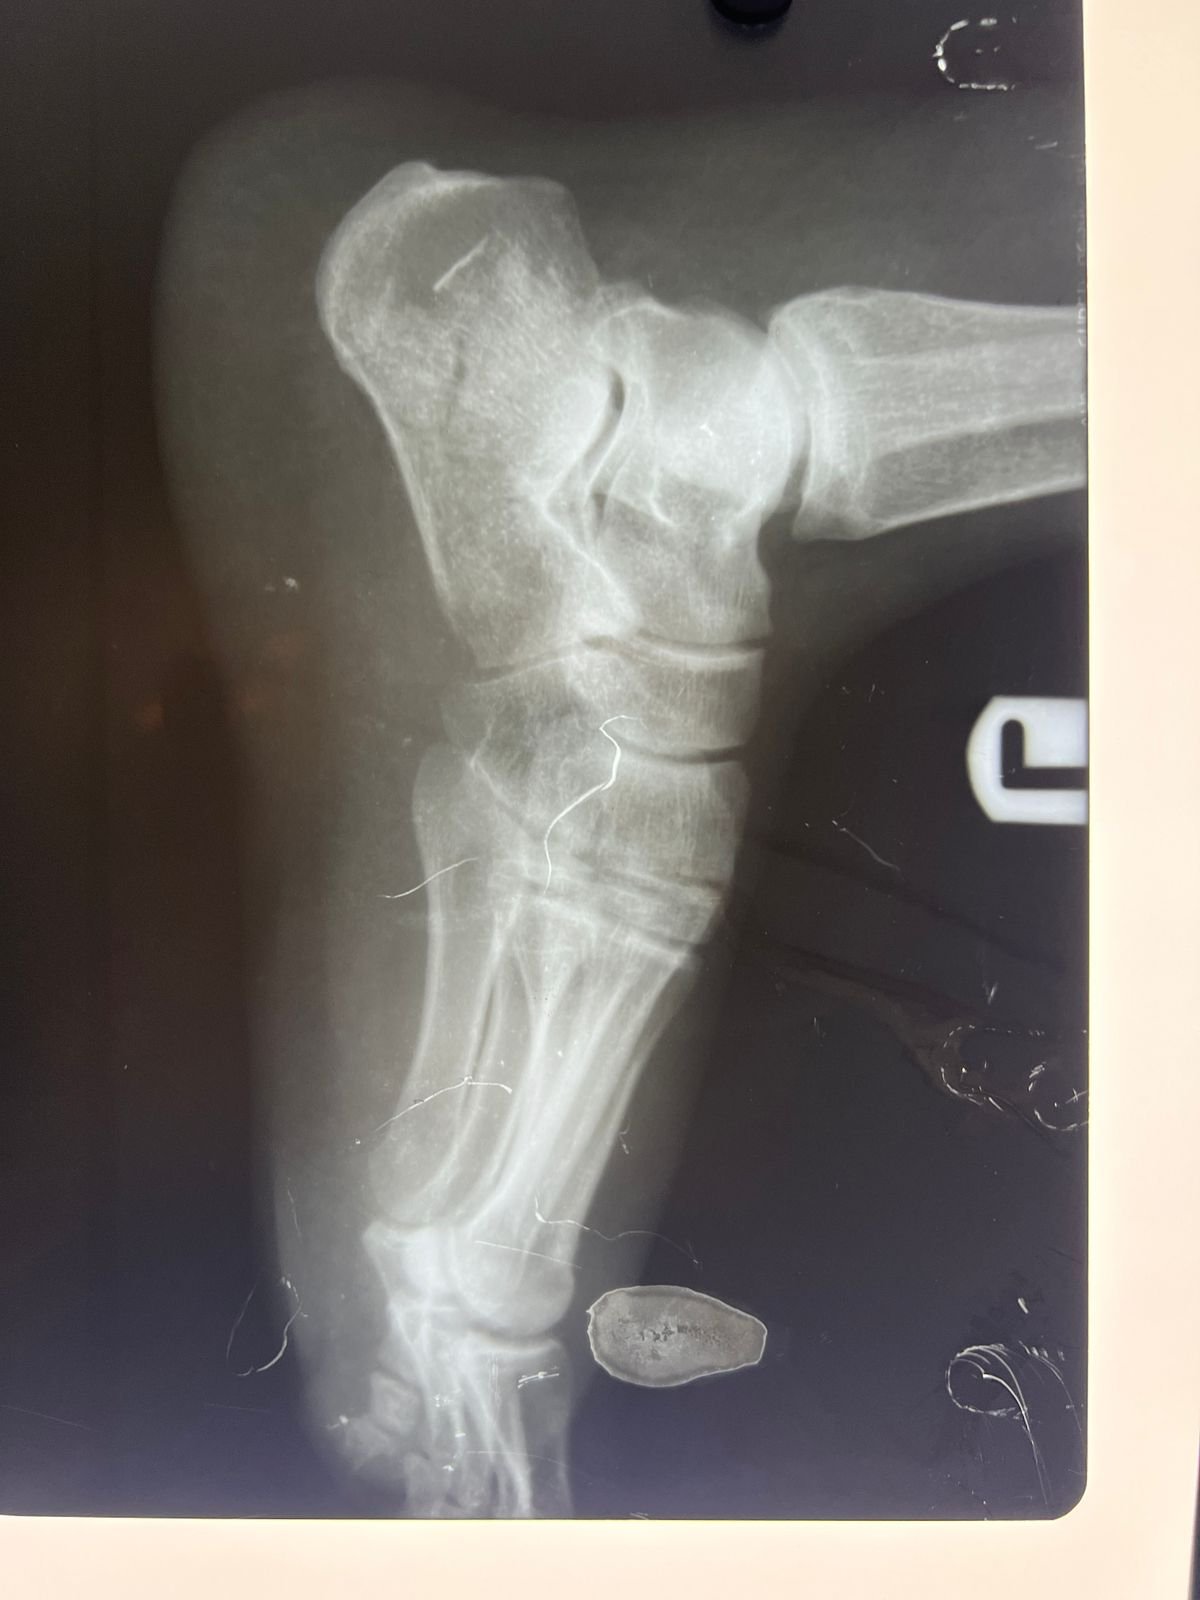

Pre op & postop X-ray compound fracture lower tibia

& fibula | Heal fracture pre & postop | Clavicle